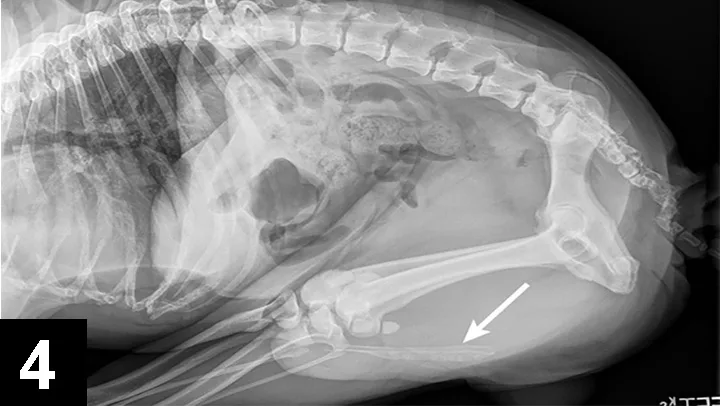

Cystine crystals are flat, colorless, and hexagonal. The sides of the hexagon may or may not be of equal lengths, and the crystals tend to aggregate in urine sediment, resulting in a layered appearance (Figure 2). Cystine uroliths have intermediate radiodensity; they are typically less radiodense than calcium oxalate and struvite uroliths but more so than ammonium urate uroliths (Figures 3 and 4). In some cases, contrast urethrocystography or ultrasonography may be necessary to visualize uroliths. Cystine uroliths are usually smooth and spherical and range in size from less than 1 mm to greater than 3 cm in diameter. Affected dogs frequently present with multiple cystine uroliths (Figure 5). Secondary urinary tract infections are uncommon.

FIGURE 3 Lateral radiograph of a 5-year-old, castrated English bulldog with multiple cystine uroliths in the kidneys, bladder, and urethra (arrow).